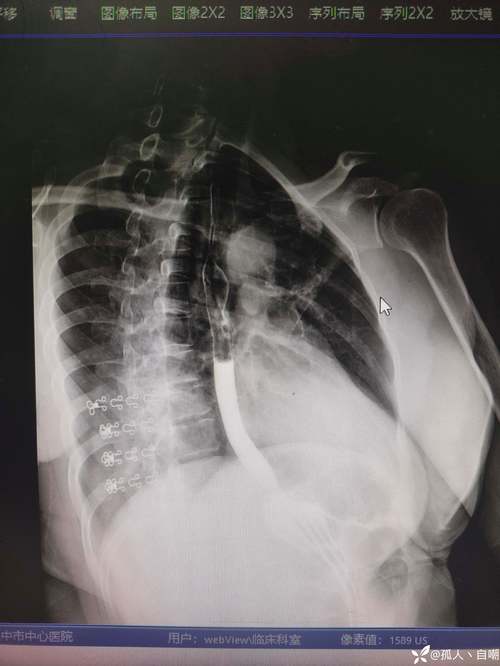

食管的解剖路径:从颈部向下延伸,经胸骨后、纵隔内,最终进入腹腔。其位置随呼吸和吞咽动作略有移动,但始终保持与脊柱前方的紧密关系。食管的三个生理狭窄部位:1. 食管入口:位于咽与食管交接处(约第6颈椎下缘),是食管最狭窄的部位,直径约1.5厘米。此处易因食物滞留引发感染或损伤。2. 主动脉弓...。

食管的三个生理狭窄位置如下:第一个狭窄位于食管起始处,即食管与咽腔的连接部位,距离中切牙约15厘米。此处是食管最狭窄的区域,食物通过时易受阻,可能引发吞咽困难。此狭窄也是食管异物滞留或损伤的高发部位。第二个狭窄位于食管与左主支气管交叉处,距离中切牙约25厘米。此处是食管穿过纵隔的固定部位,...。

食管的三个狭窄位置及临床意义如下:第一个狭窄位于食管的起始处,即咽与食管的连接部位,距中切牙约15厘米。此处是食管最狭窄的区域之一,与吞咽动作的起始直接相关。食物从咽部进入食管时需通过此狭窄,因此其解剖结构对吞咽功能至关重要。若此处发生病变,如异物滞留、炎症或肿瘤,会直接导致吞咽困难,甚至引发呛咳或窒息风险。第。